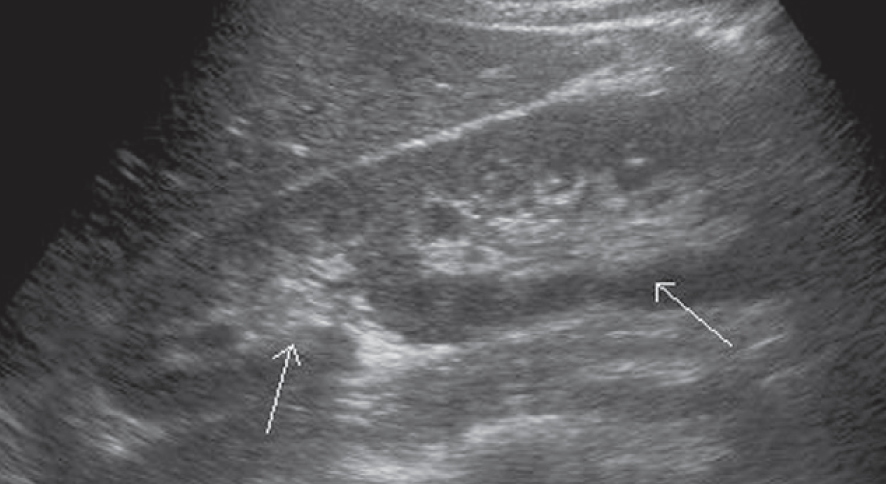

1-Hypertrophied column of Bertin

أعتقد بأن هذا من أهم المتغيرات التي قد يشتبه في كونها ورم. هي ببساطة تضخم لنسيج الكلية parenchyma إلى الداخل sinuses مرورا بين الأهرامات الكلوية medullary pyramids.

يميزه تناسق echogenicity بينه وبين باقي parenchyma بالإضافة لعدم وجود ارتفاع أو تغير ملحوظ في قراءات colour Doppler. غالبا لا يزيد عرضه عن ٣ سم.